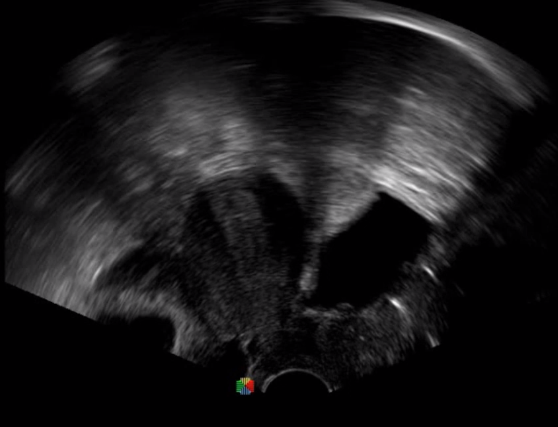

取卵臨床圖